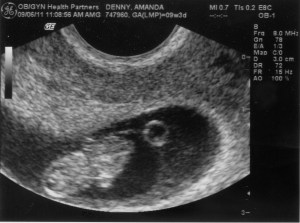

Well kids, it’s week 11 or so, sorry for slacking so much, but apparently this is the slower season for changes in our Baby D’s (my new nickname) development. Apparently toes are forming along with other appendages, and pretty much like every week in baby iPhone app, it’s “a big week for growth”. I’m starting to wonder when their going to say “Nothing really happened this week, enjoy that elbow in your bladder.” I’m sure that is what my wife will eventually be sure to remind me of sometime around the holidays this year. Per her request, I’m going to officially apologize for my obvious grammatical mistakes, that apparently are driving her crazy.